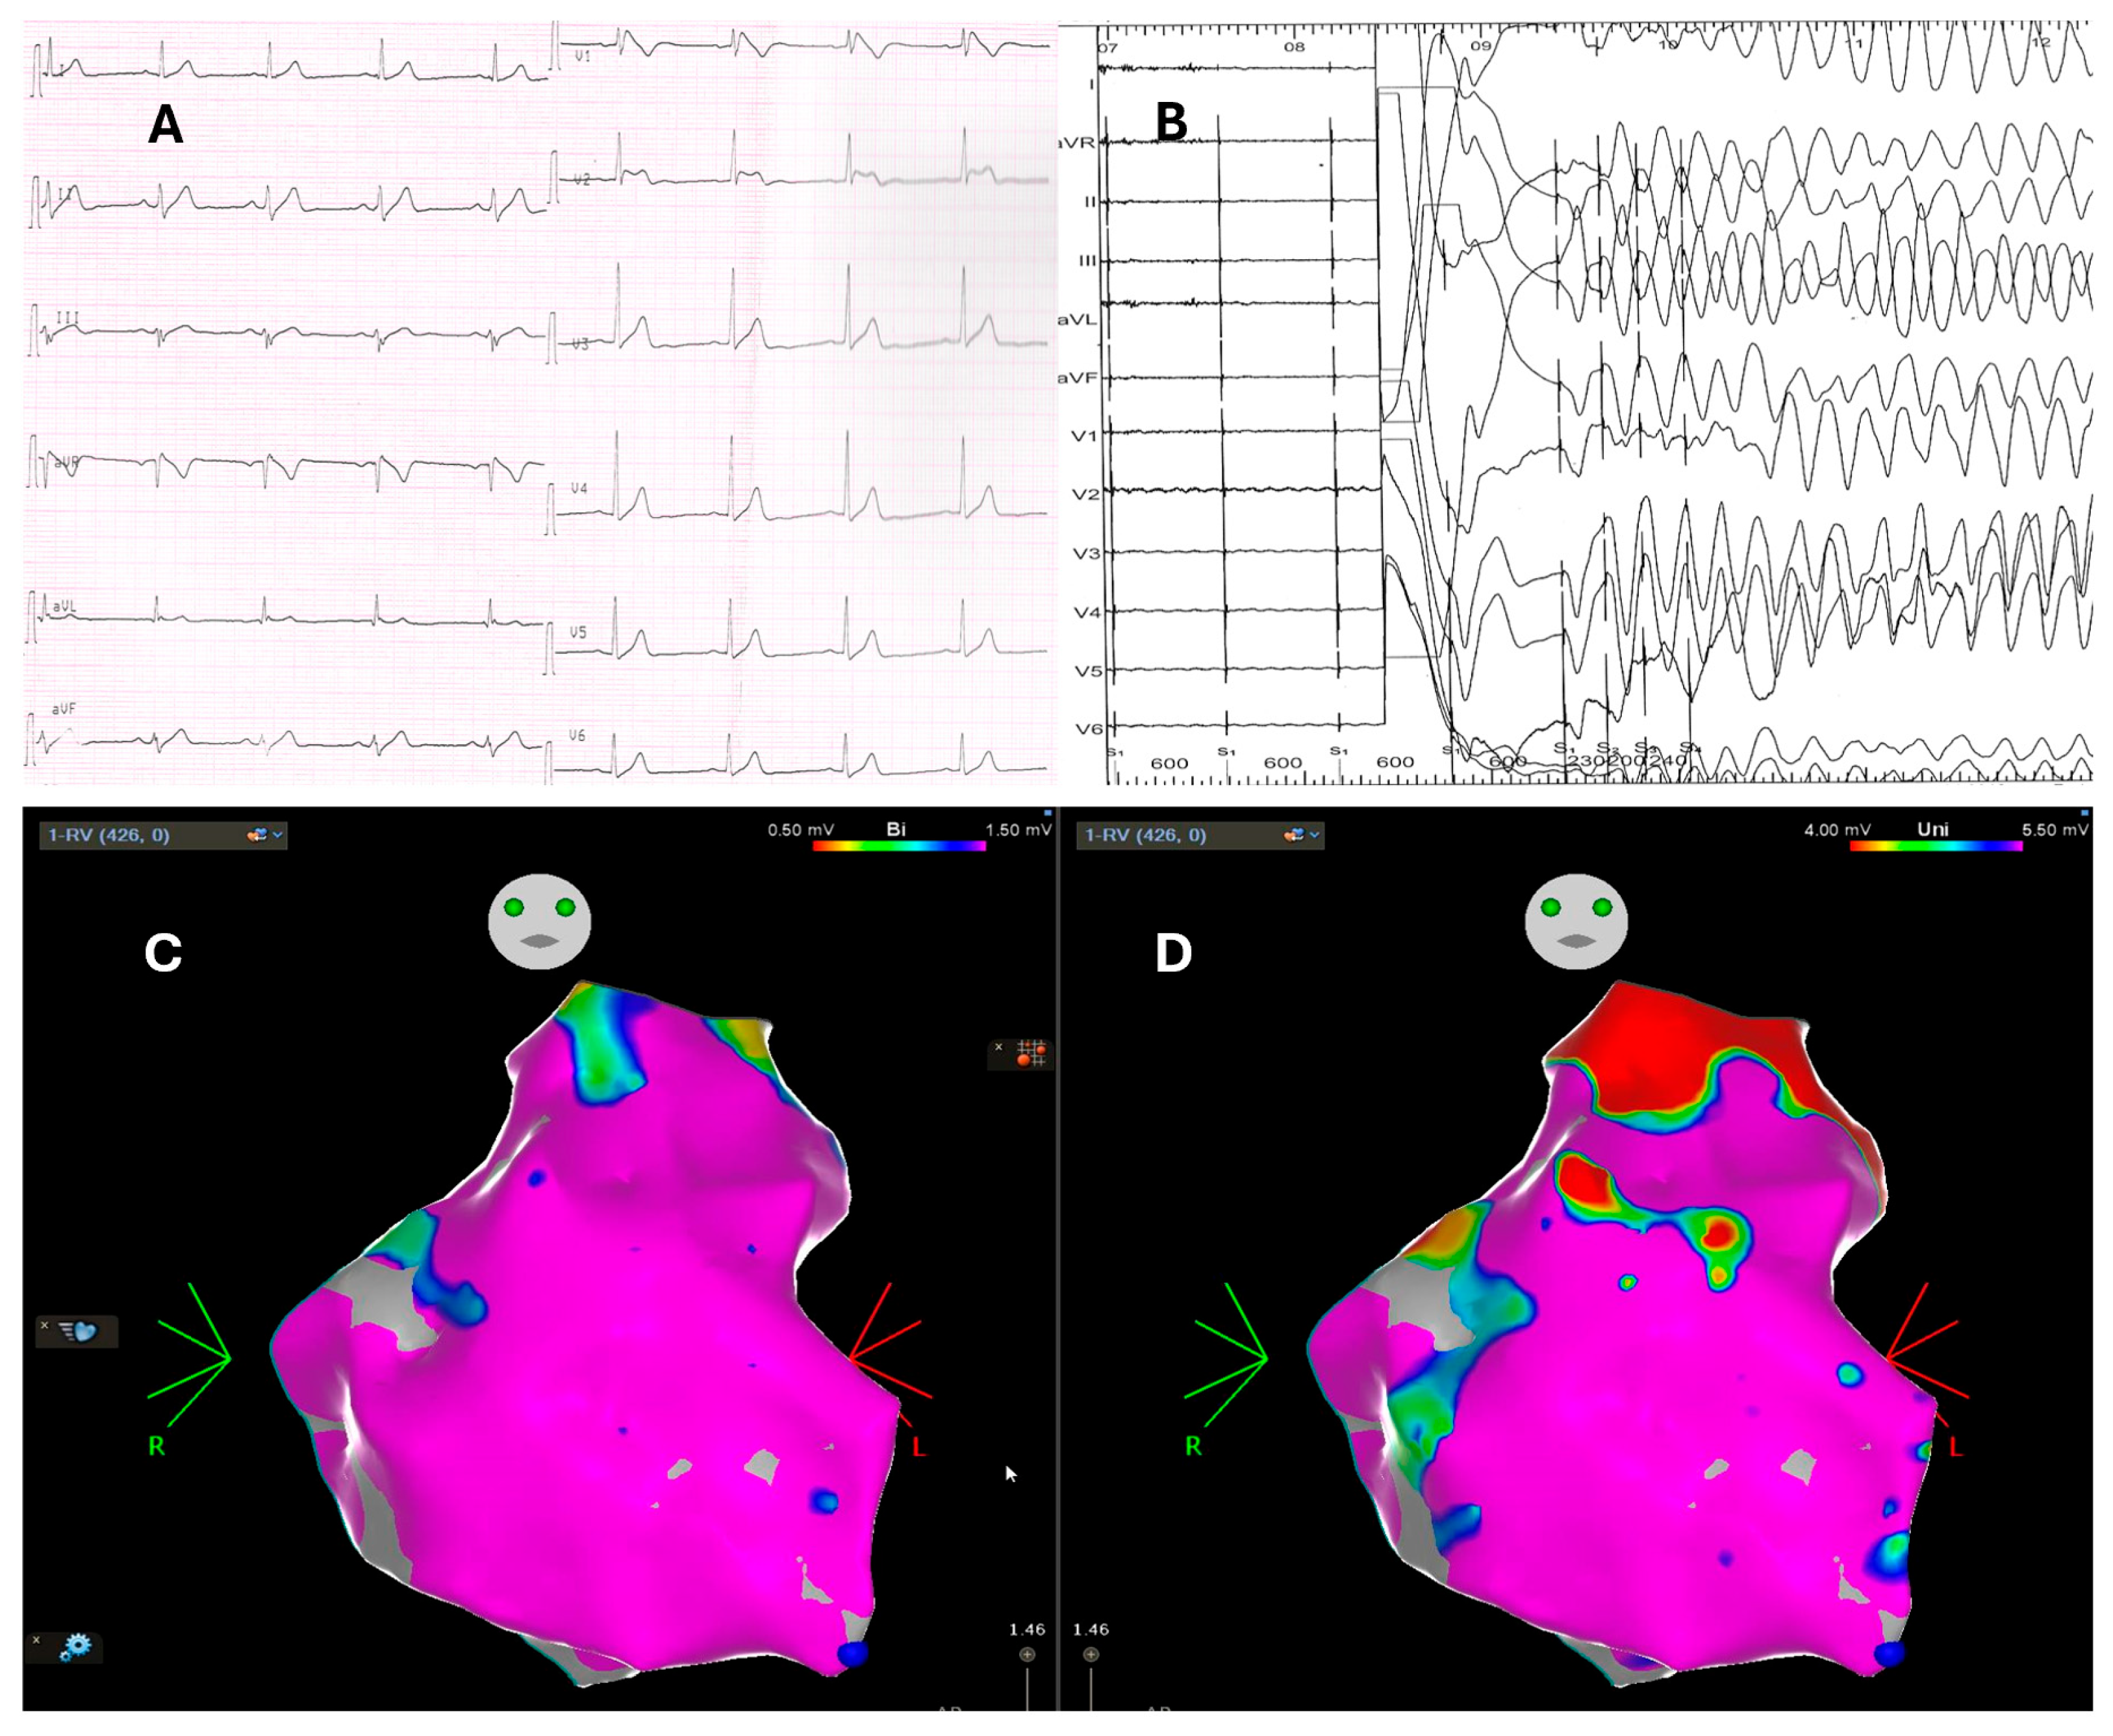

- Pieroni, M.; Notarstefano, P.; Oliva, A.; Campuzano, O.; Santangeli, P.; Coll, M.; Nesti, M.; Carnevali, A.; Fraticelli, A.; Iglesias, A.; et al. Electroanatomic and Pathologic Right Ventricular Outflow Tract Abnormalities in Patients With Brugada Syndrome. J. Am. Coll. Cardiol. 2018, 72, 2747–2757. [Google Scholar] [CrossRef]

- Pappone, C.; Ciconte, G.; Manguso, F.; Vicedomini, G.; Mecarocci, V.; Conti, M.; Giannelli, L.; Pozzi, P.; Borrelli, V.; Menicanti, L.; et al. Assessing the Malignant Ventricular Arrhythmic Substrate in Patients With Brugada Syndrome. J. Am. Coll. Cardiol. 2018, 71, 1631–1646. [Google Scholar] [CrossRef]

- Lambiase, P.D.; Ahmed, A.K.; Ciaccio, E.J.; Brugada, R.; Lizotte, E.; Chaubey, S.; Ben-Simon, R.; Chow, A.W.; Lowe, M.D.; McKenna, W.J. High-density substrate mapping in brugada syndrome: Combined role of conduction and repolarization heterogeneities in arrhythmogenesis. Circulation 2009, 120, 106–117. [Google Scholar] [CrossRef]

- Brugada, J.; Pappone, C.; Berruezo, A.; Vicedomini, G.; Manguso, F.; Ciconte, G.; Giannelli, L.; Santinelli, V. Brugada Syndrome Phenotype Elimination by Epicardial Substrate Ablation. Circ. Arrhythm. Electrophysiol. 2015, 8, 1373–1381. [Google Scholar] [CrossRef]

- Pappone, C.; Brugada, J.; Vicedomini, G.; Ciconte, G.; Manguso, F.; Saviano, M.; Vitale, R.; Cuko, A.; Giannelli, L.; Calovic, Z.; et al. Electrical Substrate Elimination in 135 Consecutive Patients with Brugada Syndrome. Circ. Arrhythm. Electrophysiol. 2017, 10, e005053. [Google Scholar] [CrossRef]